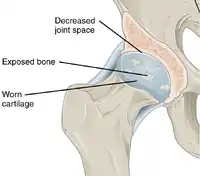

Histopathology of osteoarthrosis of a knee joint in an elderly female In a healthy joint, the ends of bones are encased in smooth cartilage. Together, they are protected by a joint capsule lined with a synovial membrane that produces synovial fluid. The capsule and fluid protect the cartilage, muscles, and connective tissues.

In a healthy joint, the ends of bones are encased in smooth cartilage. Together, they are protected by a joint capsule lined with a synovial membrane that produces synovial fluid. The capsule and fluid protect the cartilage, muscles, and connective tissues. With osteoarthritis, the cartilage becomes worn away. Spurs grow out from the edge of the bone, and synovial fluid increases. Altogether, the joint feels stiff and sore.